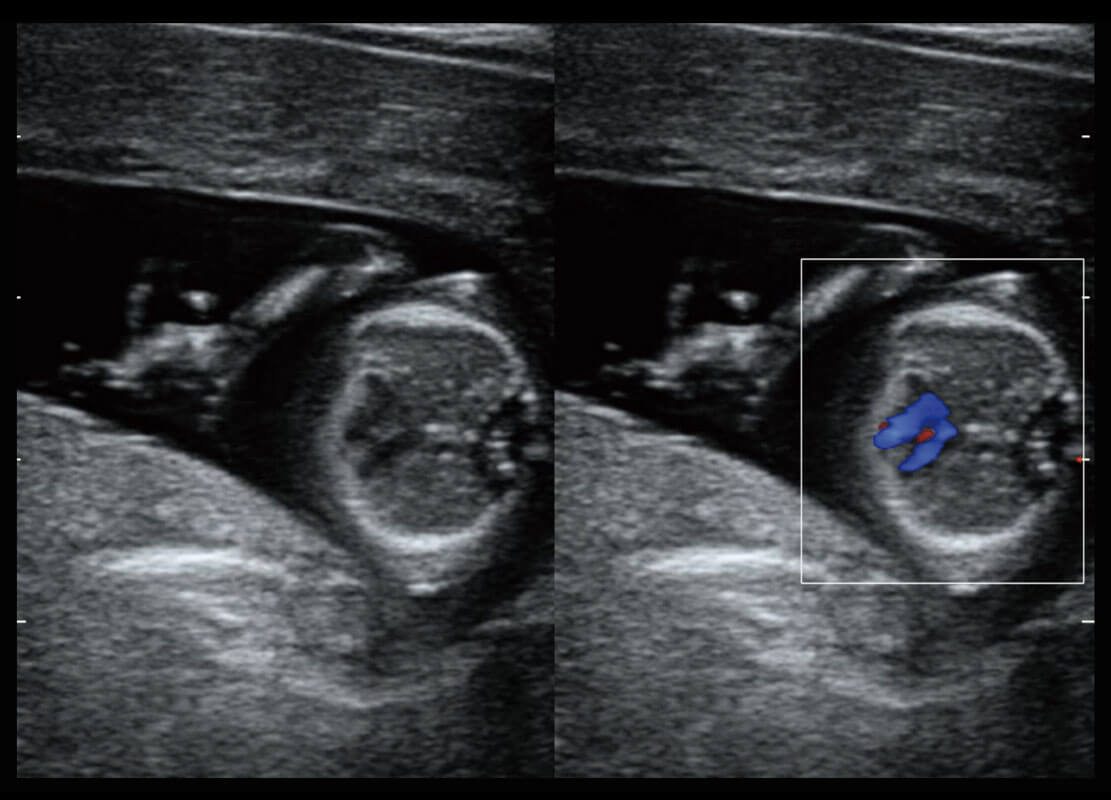

P60搭载宽频带线阵探头、宽景成像、弹性成像技术,为您提供乳腺应用方案。P60支持高频相控阵探头、线阵探头、腹部高频探头、腹部微凸探头等,丰富的探头群搭载敏感的彩色血流成像,适用于新生儿多种脏器检测要求,满足新生儿筛查需求。

乳腺导管癌

乳腺癌显微血流

新生儿肝血管癌

新生儿脊髓圆锥

新生儿心脏